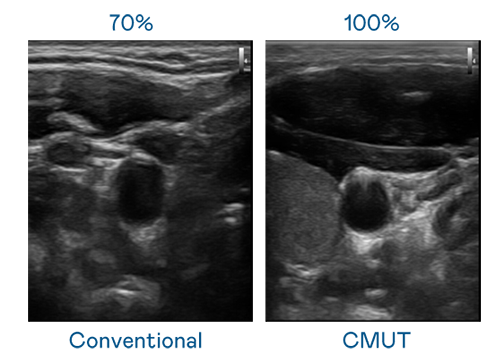

CMUT 技术是一种用电容式微机电元件来产生超音波讯号的技术。与传统 PZT 压电式技术相比,CMUT 频宽增加 30%,更宽频的超音波讯号让影像解析度大幅提升,是实现高影像品质医疗超音波扫描、促进精准医疗发展的关键技术。

大频宽带来超清晰影像

超音波影像的解析度高低,首先取决于探头能发出的讯号频宽。UU国际 CMUT 可提供高清晰的超音波讯号,提供高频宽、高灵敏度、影像纹理细节更高的超音波影像,协助医护人员缩短影像判读时间及利用精准的医疗影像进行诊断。